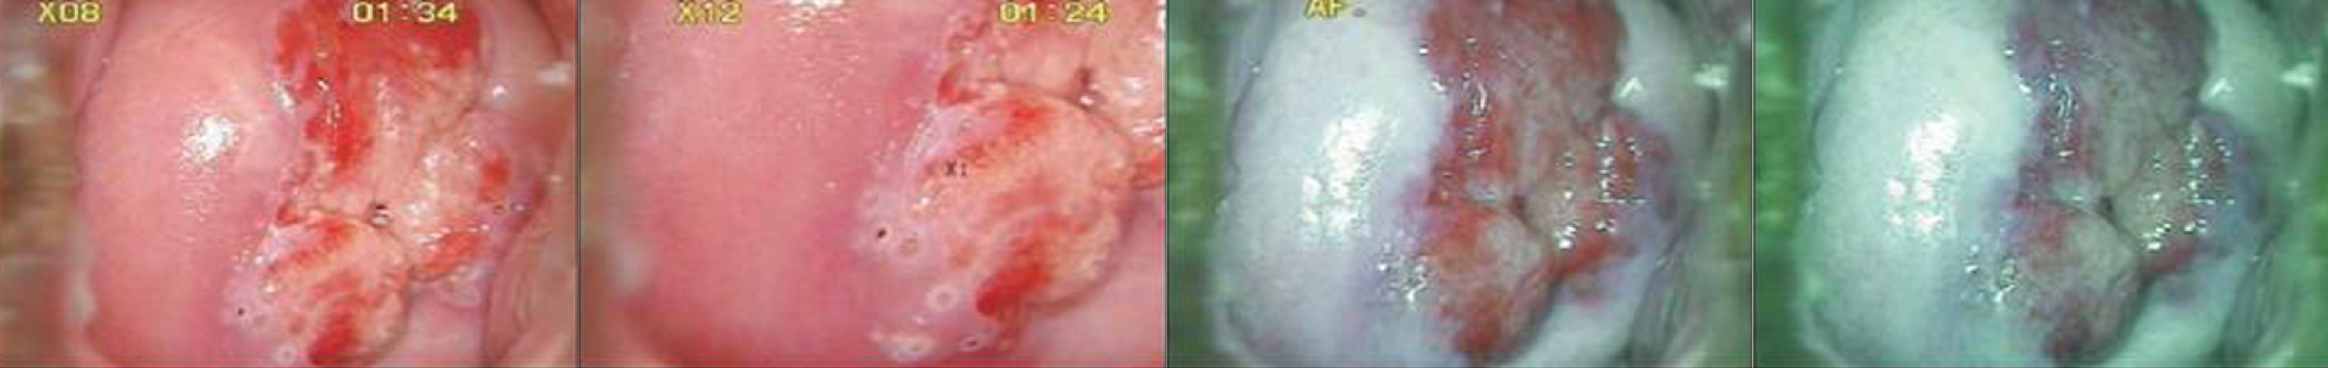

通过滤镜更加直观识别组织

采用电子绿色滤镜功能,可有效识别上皮组织细节层次和细小血管的表现,满足临

床对早期癌变观察检查和诊断的需要